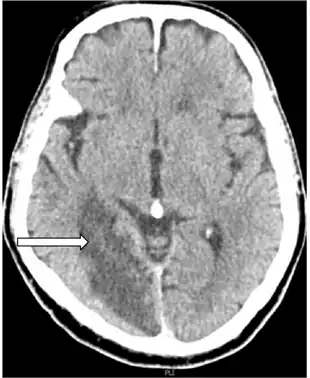

Anton syndrome because of Bilateral Ischemic Occipital Lobe Strokes-image indicates nonhemorrhagic cerebral infarction arrow